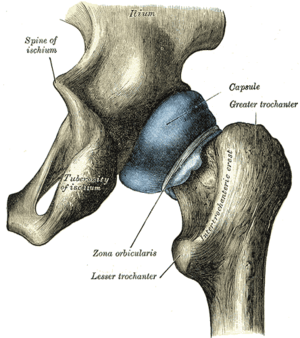

Am Aufbau des Gegenstückes, der Hüftgelenkpfanne (Acetabulum), sind alle drei Beckenknochen beteiligt: Das Dach wird vom Darmbein (Os ilium) gebildet, das Schambein (Os pubis) begrenzt vorne (ventral) und das Sitzbein (Os ischii) hinten-unten (dorsokaudal) den Rand des Beckens mit seiner Vertiefung, das so genannte Acetabulum („Essignäpfchen“).

Stellt man sich die Pfanne als hohle Halbkugel vor, beträgt ihr Radius beim Menschen je nach Körpergröße etwa 2,7 Zentimeter. Eine bogenförmige Faserknorpellippe (Labrum acetabuli bzw. Limbus acetabuli) geht jedoch stellenweise über den Äquator der Halbkugel hinaus und umgreift regelrecht den Oberschenkelknochenkopf. Daher spricht man beim Hüftgelenk auch von einem Nussgelenk (Sonderform des Kugelgelenkes). Zum Schambeinloch (Foramen obturatum) ausstrahlend ist die Pfannenlippe hingegen unterbrochen (Incisura acetabuli), sodass sie eine halbmondförmige Gestalt annimmt. Dieser unterbrochene Teil der Pfanne wird von einem Querband (Ligamentum transversum acetabuli) überbrückt.

Umhüllt wird das Hüftgelenk von der kräftigsten Gelenkkapsel des menschlichen Körpers, der straffen Hüftgelenkskapsel (Capsula articularis coxae). Sie wird über innerhalb der Kapsel gelegene Bänder stabilisiert und in der Mitte vom Ringband umgurtet.

Die äußere Schicht der Gelenkkapsel (Membrana fibrosa capsulae) entspringt am Limbus acetabuli und überdeckt trichterförmig fast vollständig den Oberschenkelknochenhals, um vorne an der Linie zwischen den beiden Oberschenkelrollhügeln (Linea intertrochanterica) zu inserieren. Hinten (dorsal) ist die Ansatzlinie etwa fingerbreit oberhalb des Randes (Crista intertrochanterica) zwischen den Oberschenkelknorren (Trochanter major und Trochanter minor) entfernt.